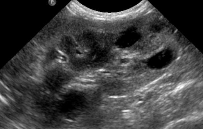

DX? (reins)

polykystose

=> multiples kystes rénaux (zones anéchogènes)